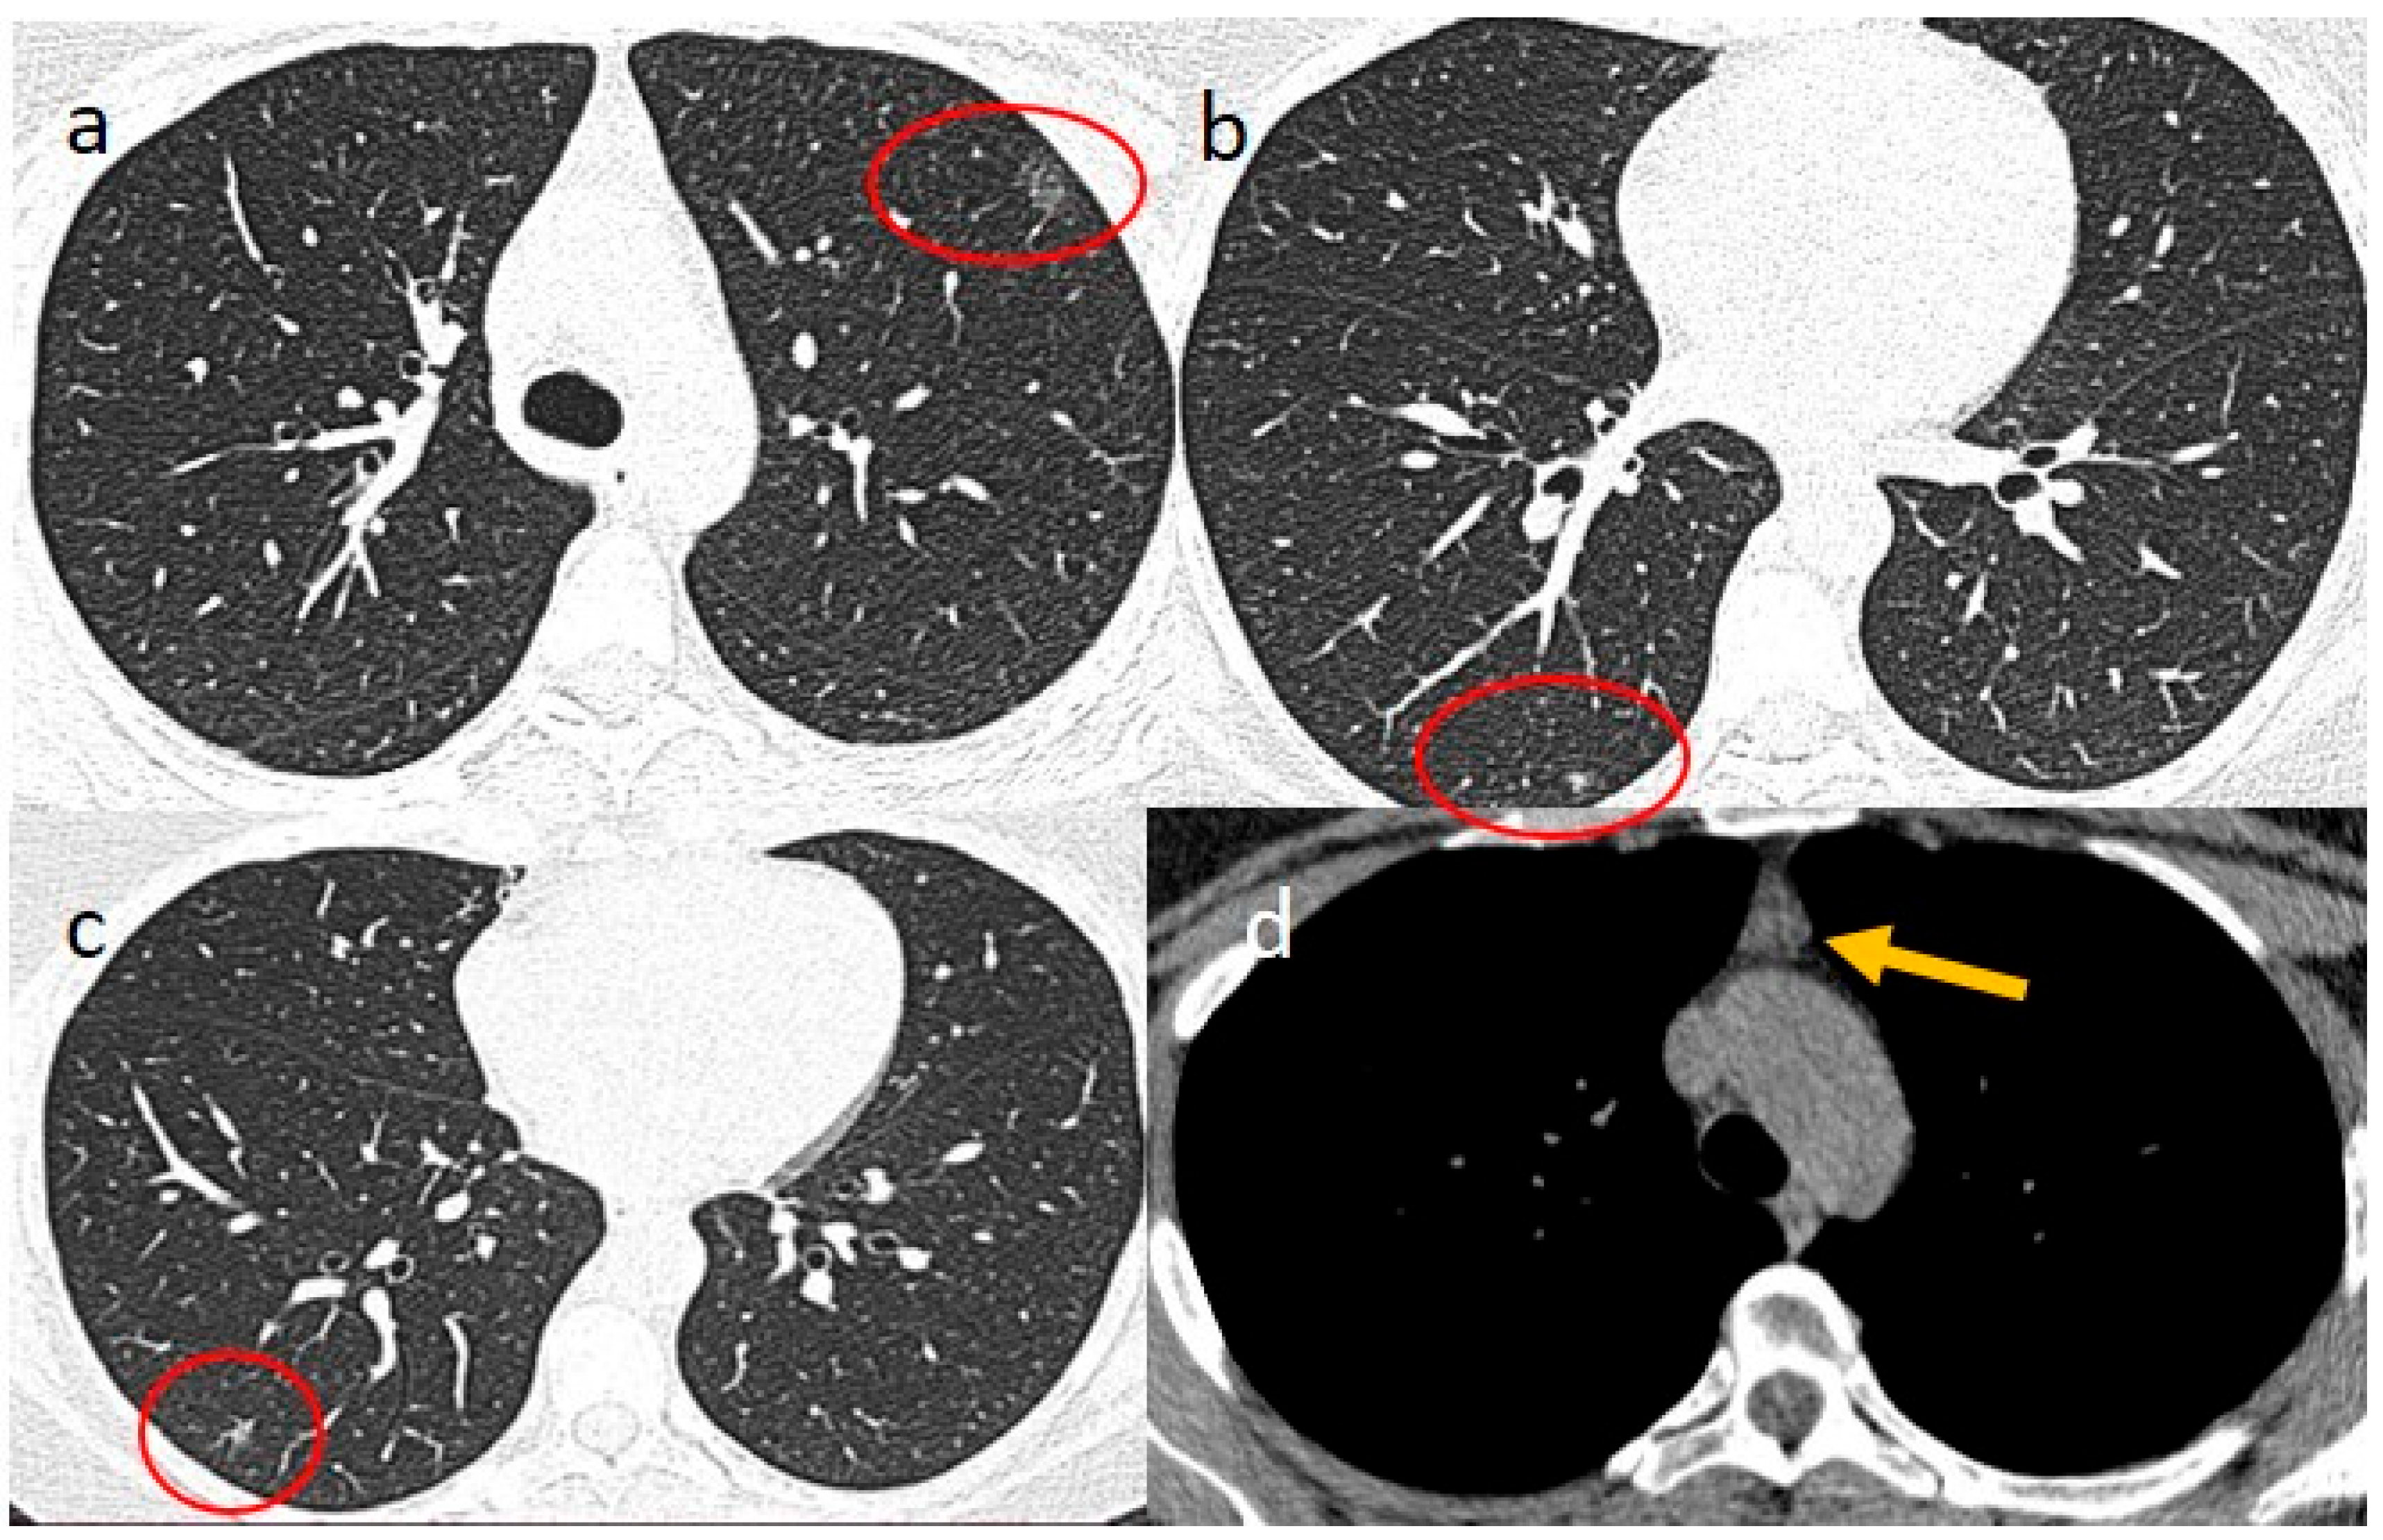

2. Case Presentations

- Brogna, B.; Bignardi, E.; Salvatore, P.; Alberigo, M.; Brogna, C.; Megliola, A.; Musto, L. Unusual presentations of COVID-19 pneumonia on CT scans with spontaneous pneumomediastinum and loculated pneumothorax: A report of two cases and a review of the literature. Heart Lung 2020, 49, 864–868. [Google Scholar] [CrossRef]